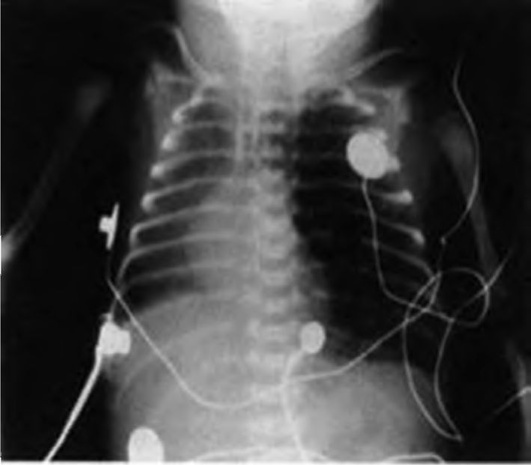

Клиническая картина

Заболевание развивается внезапно: гипертермия, одышка, выраженное беспокойство. В легких на выдохе выслушивают свистящие хрипы, активизирована работа дыхательных мышц. Работа межреберных и диафрагмальных мышц, участвующих в акте дыхания, при остром бронхиолите увеличена в среднем в 6 раз. Дыхание становится частым и поверхностным, создается впечатление, что грудная клетка эмфизематозна (рис. 3-4).

image

Рис. 3-4. Схема клинических проявлений бронхиолита

При рентгенологическом исследовании выявляют отчетливую эмфизематозность легочных полей.